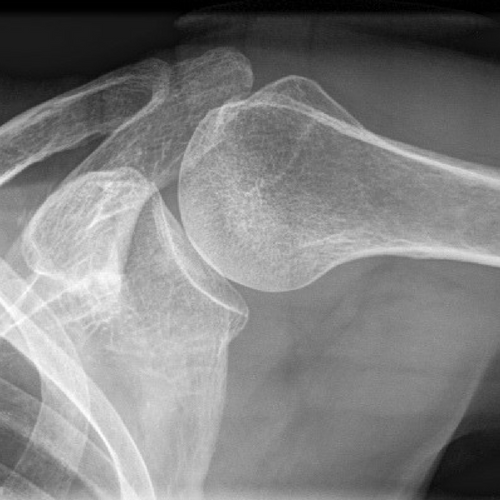

Frozen Shoulder: Does it Really Thaw?

Frozen shoulder is a very painful shoulder condition, yet most people forego getting treatment. They simply try and “wait it out.” It has always shocked me how long patients tolerate the pain of frozen shoulder before getting treatment. But once they start the process of physical therapy, every single patient says: “Why didn’t I do this sooner?”…